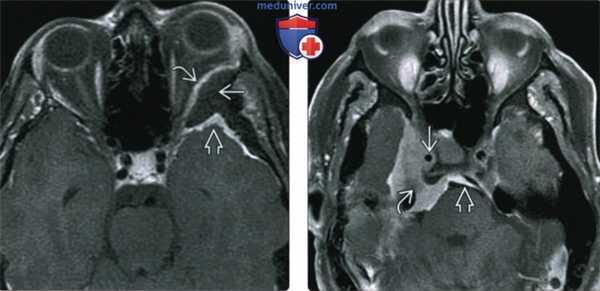

(Слева) При MPT Т1 ВИ FS с КУ в аксиальной проекции у пациента с левосторонним экзофтальмом определяется плоская (en plaque) менингиома левого крыла клиновидной кости: наблюдается выраженный гиперостоз, но виден лишь тонкий контрастный ободок внутри-глазничного и внутричерепного компонентов опухоли.

(Справа) При МРТ Т1 ВИ FS с КУ в ксиальной проекции определяется менингиома среднего отдела основания черепа, окружающая правую внутреннюю сонную артерию и вызывающая сужение последней. Через porus trigeminus опухоль проникает в предмостовую цистерну. С медиальной стороны виден «дуральный хвост».

(Слева) При MPT Т2 ВИ в аксиальной проекции у этого же пациента определяется менингиома среднего отдела основания черепа; опухоль примерно изоинтенсивна по сравнению с серым веществом, между опухолью и смещенной височной долей видна ликворная/сосудистая щель. Небольшой компонент опухоли в задней черепной ямке деформирует мост.

(Справа) При корональной МРТ Т1 ВИ FS с КУ на медиальной поверхности пирамиды височной кости определяется экстрааксиальное объемное образование, прорастающее во внутренний слуховой проход и яремное отверстие. Виден гиперостоз верхней стенки внутреннего слухового прохода.